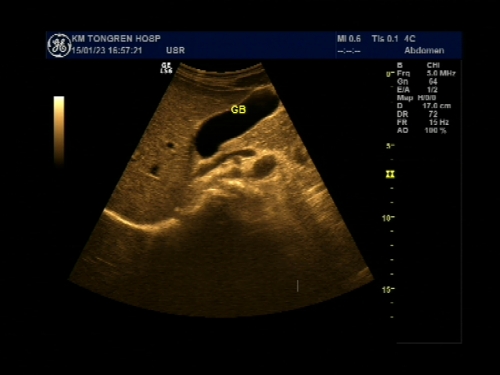

超声声像图能显示肝脏切面形态、大小、肝内实质结构、管道系统及肝周邻,并能根据肝内管道系统区分肝脏各叶、各段,对病变进行定位诊断。彩色多普勒超声能显示肝脏的血流,并能对肝脏的血流动力学参数进行测定,不仅能诊断肝脏的血管病变,还能了解正常肝脏及病变肝脏的血供及回流状态,目前已成为临床诊断肝脏疾病的常规检查方法。

彩色多普勒超声扫查

彩色多普勒能量图